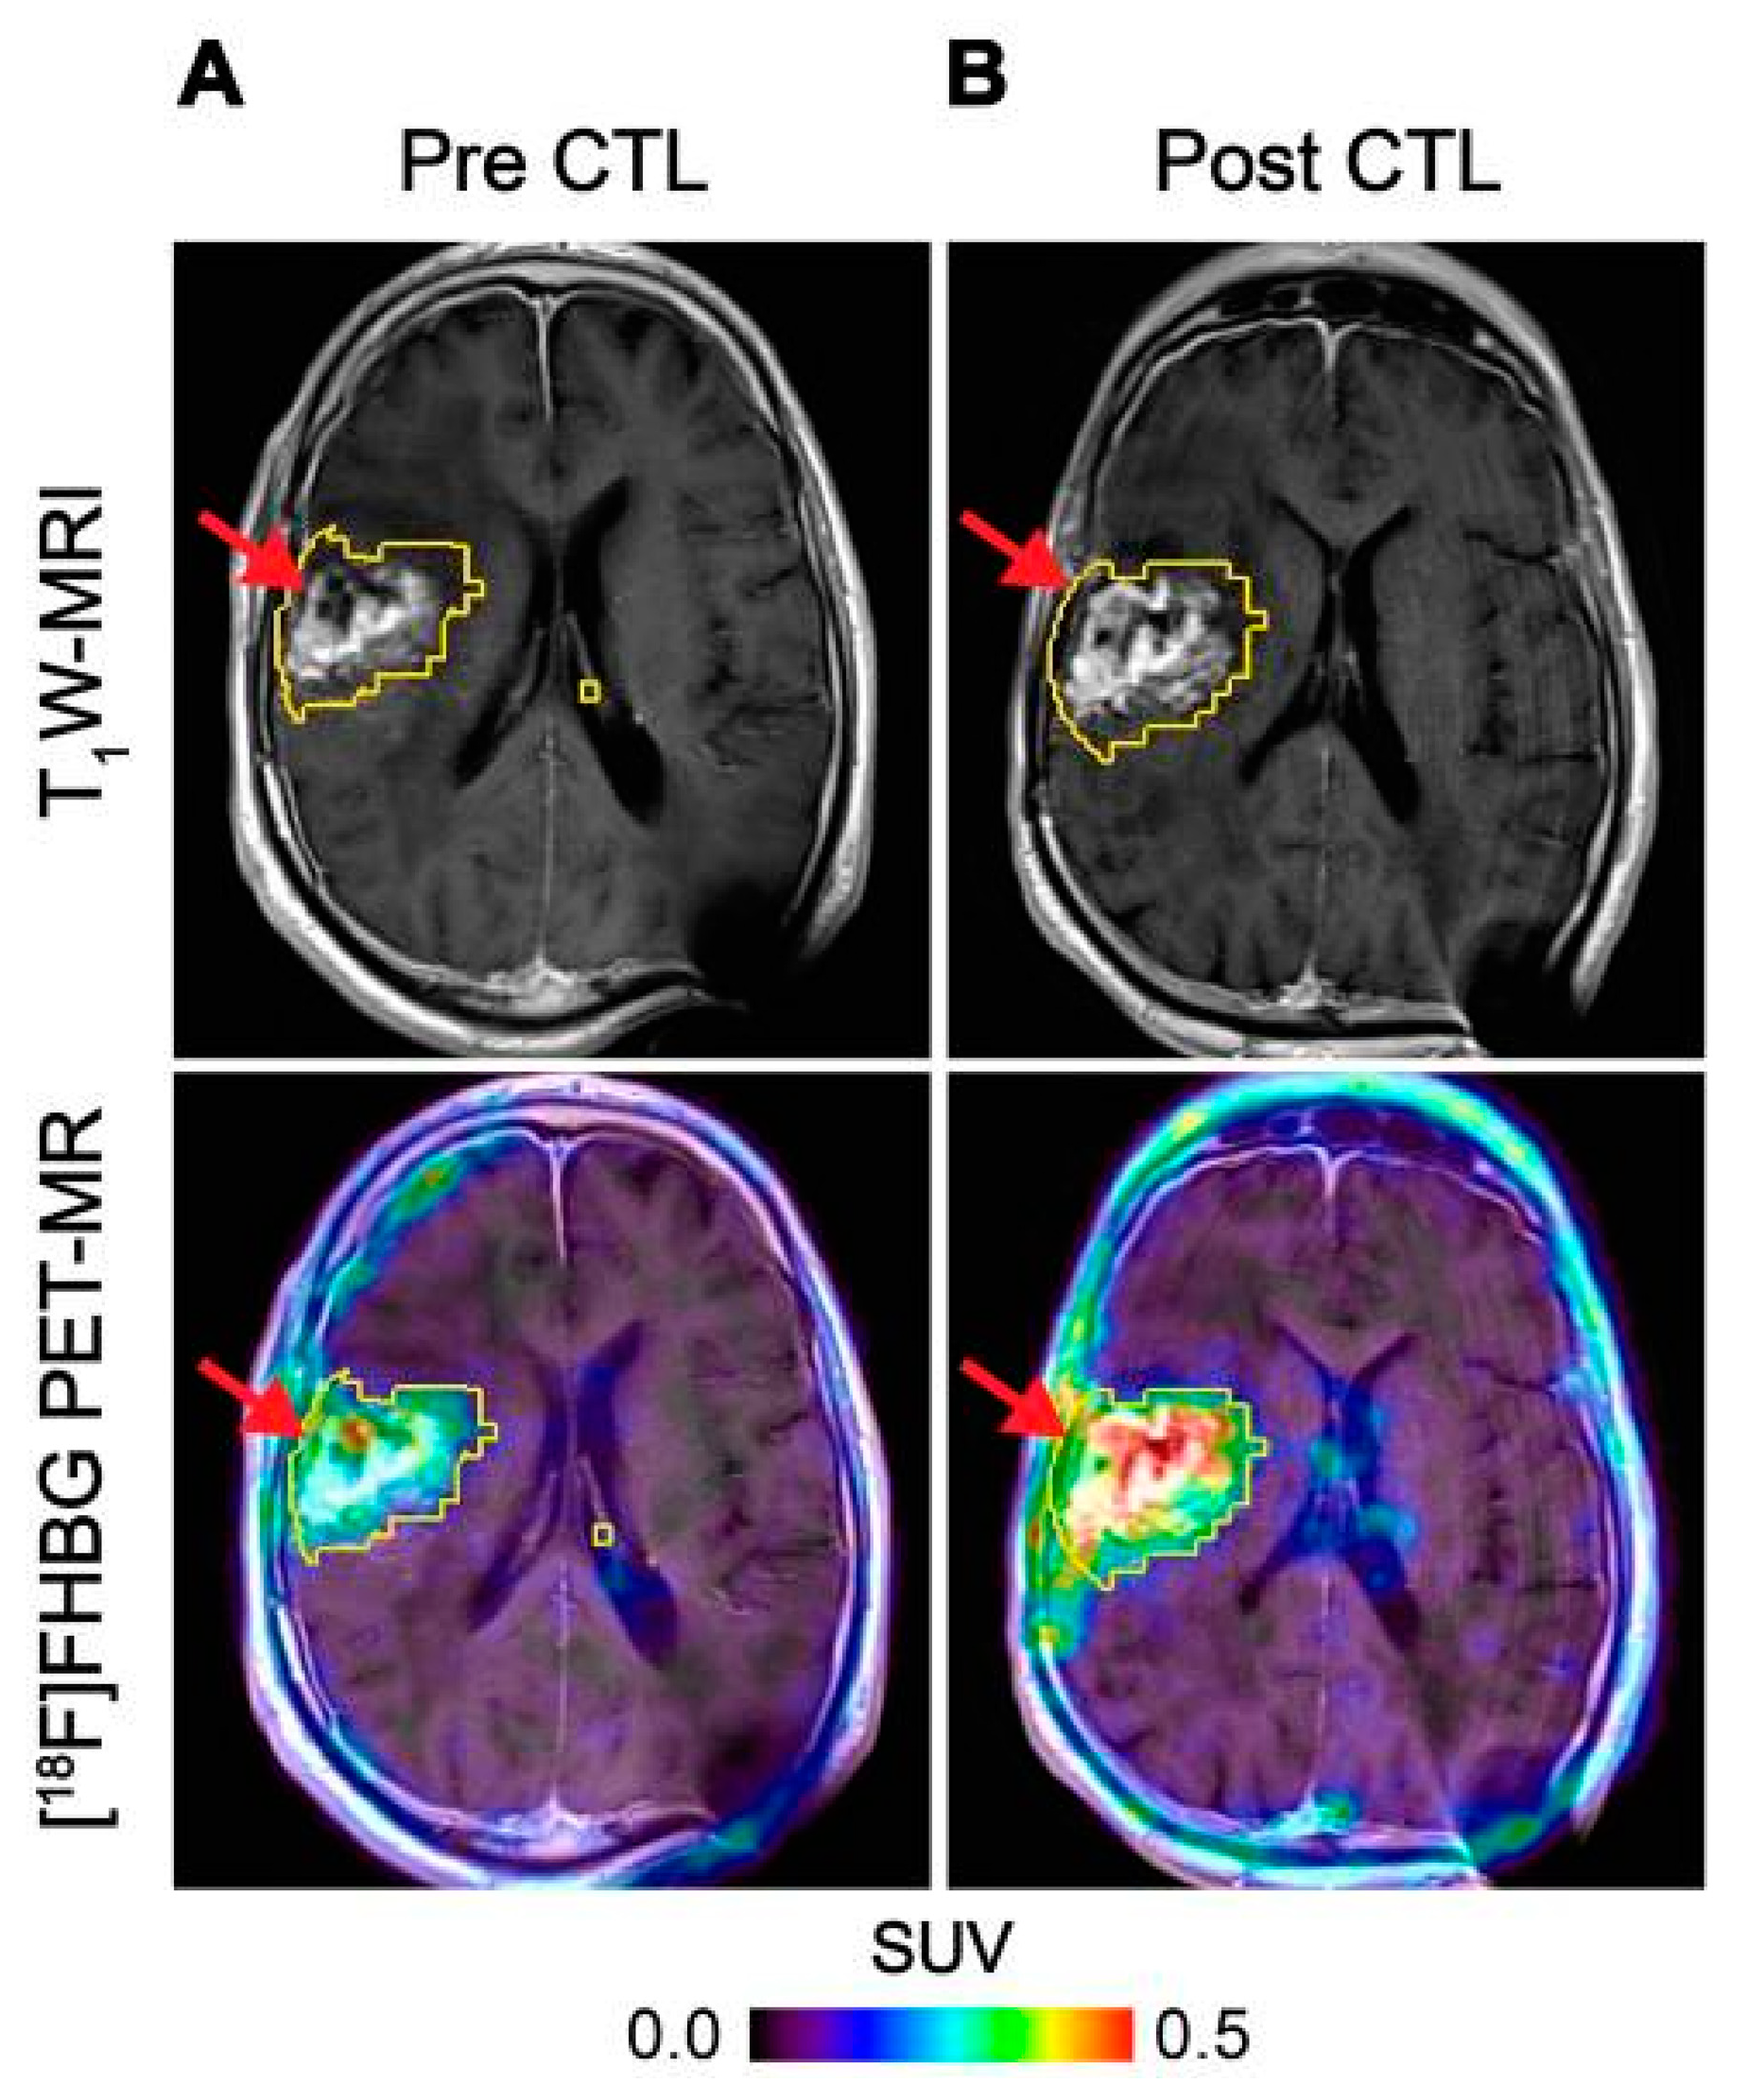

HSV1-tk is an intracellular enzyme with high selectivity for the thymidine analogue ganciclovir, an inhibitor of viral DNA replication commonly prescribed to treat an HSV infection [56]. Radiolabelled ganciclovir analogues in combination with HSV1-tk expression have been utilised extensively as reporter systems for imaging [57]. The first human application of this approach used PET imaging with 9-[4-[18F]fluoro-3-(hydroxymethyl)butyl]guanine ([18F]FHBG) to track HSV1-tk transduced cytotoxic T-cells (CTLs) administered for treatment of recurrent high grade glioma [50]. The concept was expanded to monitor CTL trafficking, survival, and proliferation in seven patients with recurrent high-grade glioma that were resistant to conventional therapies by performing PET imaging with FHBG before and after intracerebral CTL infusion, where a significant increase in [18F]FHBG total activity was observed representing the CTL trafficking to tumours [51] (Figure 3). Therapeutic concentrations of ganciclovir analogues can be used to selectively kill HSV1-tk transduced cells. This additional feature provides a safety switch to stop the activity of the transferred cells if desired as shown in preclinical models [58,59], and may be particularly relevant in the regulation and control of CAR T-cells [60]. However, since HSV1-tk is a foreign protein and potentially immunogenic, there is concern that expression of this reporter gene may affect survival of the transduced cells once injected into patients as they may be vulnerable to T-cell mediated killing [61].

Figure 3.

Imaging of HSV1-tk gene reporter expression in genetically modified CTLs with [18F]FHBG. [18F]FHBG-PET imaging was performed in a patient with recurrent glioblastoma multiforme tumour in the right frontoparietal lobe before (A) and 1 week after (B) CTL infusions. Allogeneic CTLs and IL-2 were injected intratumorally (red arrows). Tumour recurrence was monitored by T1-weighted (T1W) MRI (top panels) and [18F]FHBG-PET images were fused with the MR images (bottom panels). A significant increase in [18F]FHBG uptake and PET signal was detected following CTL infusion, which was likely to be due to CTL cell trafficking. Figure reproduced from [51].